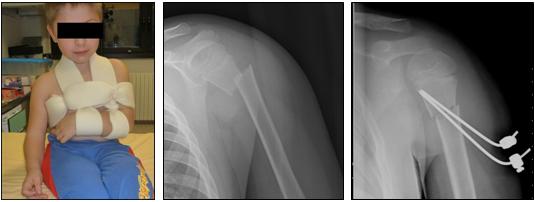

Fratture di omero - Distacchi epifisari omero prossimale

Quando la scomposizione dei frammenti è parziale, il trattamento è conservativo e si può attuare mediante applicazione di bendaggio reggi-braccio, che blocchi completamente i movimenti della scapolo-omerale (stip-stop bloccato) per 25-30 giorni.

Quando la scomposizione dei frammenti è completa, il trattamento è chirurgico con approccio deltroideo-pettorale, riduzione cruenta dei frammenti e osteosintesi mediante fili di Kirshner (percutanei o ripiegati sotto la cute) che incavigliano l'epifisi omerale.

L'immobilizzazione anche in questo caso è attuata mediante bendaggio reggi-braccio per 25-30 giorni. In alcuni casi (in genere in pazienti <10 anni) è possibile eseguire in trattamento incruento realizzando una riduzione del distacco con applicazione di trazione trascheletrica e stabilizzando la riduzione ottenuta con gesso toraco-brachiale inglobante il filo di trazione da mantenere per 30-35 giorni. Torna su